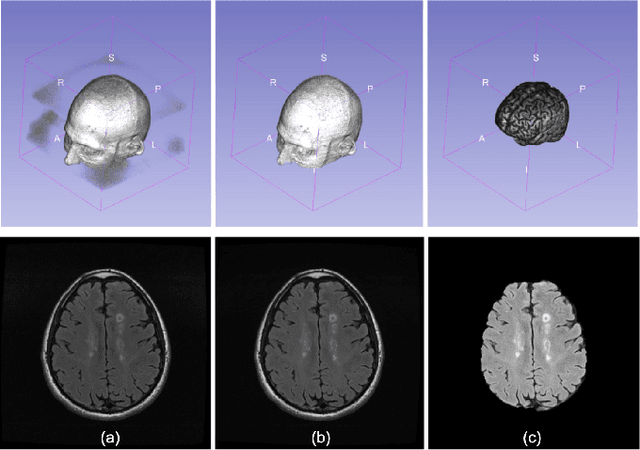

Abstract:Diffusion Weighted Imaging (DWI) is an advanced imaging technique commonly used in neuroscience and neurological clinical research through a Diffusion Tensor Imaging (DTI) model. Volumetric scalar metrics including fractional anisotropy, mean diffusivity, and axial diffusivity can be derived from the DTI model to summarise water diffusivity and other quantitative microstructural information for clinical studies. However, clinical practice constraints can lead to sub-optimal DWI acquisitions with missing slices (either due to a limited field of view or the acquisition of disrupted slices). To avoid discarding valuable subjects for group-wise studies, we propose a novel 3D Tensor-Wise Brain-Aware Gate network (TW-BAG) for inpainting disrupted DTIs. The proposed method is tailored to the problem with a dynamic gate mechanism and independent tensor-wise decoders. We evaluated the proposed method on the publicly available Human Connectome Project (HCP) dataset using common image similarity metrics derived from the predicted tensors and scalar DTI metrics. Our experimental results show that the proposed approach can reconstruct the original brain DTI volume and recover relevant clinical imaging information.